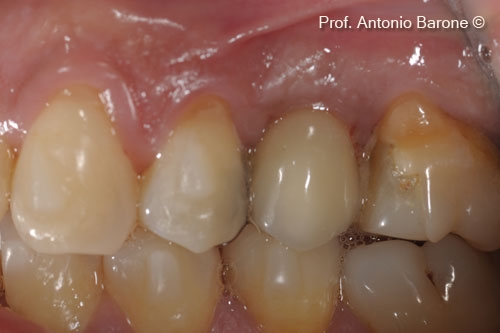

Một bệnh nhân nữ (54 tuổi) cho thấy răng bị gãy ở vị trí số 15.

Hình ảnh lâm sàng mặt nhai của một chiếc răng bị gẫy

Hình ảnh lâm sàng từ phía má của một chiếc răng bị gẫy